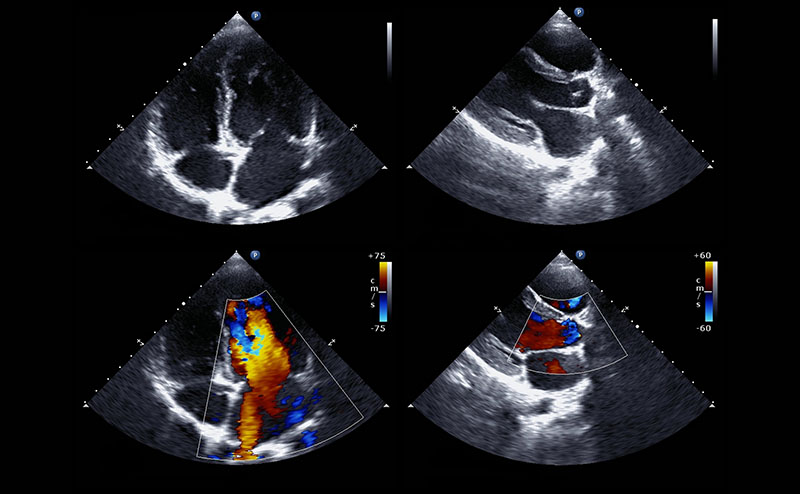

This clip displays cardiac tamponade with a large pericardial effusion. The effusion is causing diastolic collapse of the right ventricle and is concerning for tamponade physiology.

This video displays severe LV dilatation and systolic dysfunction with moderate inferior pericardial effusion. The patient ultimately was diagnosed with Anomalous Left Coronary Artery from the Pulmonary Artery (ALCAPA). In this process, the left coronary artery (LCA) arises from the pulmonary artery instead of the aorta, leading to a reversed blood flow and reduced oxygen supply to the heart muscle, causing ischemia and potentially heart failure.